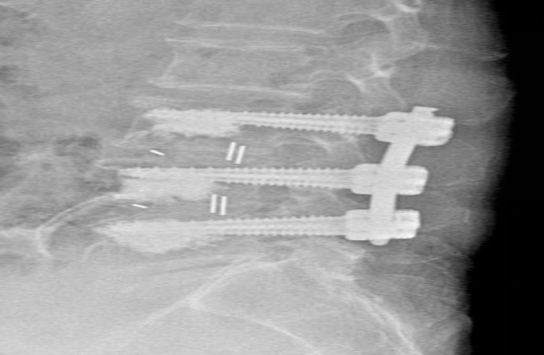

術(shù)中�����,團(tuán)隊(duì)采用先進(jìn)的骨水泥椎體強(qiáng)化技術(shù)�,有效解決了骨質(zhì)疏松導(dǎo)致的螺釘固定難題。在麻醉團(tuán)隊(duì)的精密護(hù)航下�,手術(shù)全程僅用時(shí)2小時(shí),出血量不足100ml����。術(shù)后護(hù)理團(tuán)隊(duì)實(shí)施ERAS快速康復(fù)方案,通過疼痛管理��、早期康復(fù)訓(xùn)練等舉措�����,幫助老人在術(shù)后第5天即可自主行走。

作為區(qū)域脊柱外科診療中心��,衡陽市中心醫(yī)院脊柱外科創(chuàng)新開展了“椎體強(qiáng)化聯(lián)合椎弓根螺釘固定”技術(shù)�,已為百余例高齡患者成功實(shí)施手術(shù)��。此次手術(shù)的成功�,體現(xiàn)了醫(yī)院多學(xué)科協(xié)作的優(yōu)勢,更彰顯了醫(yī)療團(tuán)隊(duì)精湛的技術(shù)�。